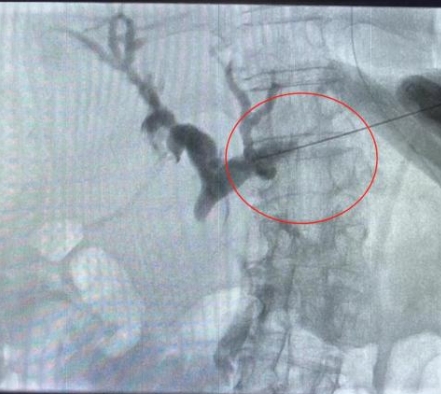

由于患者肝右葉占位巨大,完全遮擋右側(cè)穿刺路徑,左肝管為唯一穿刺路徑。介入科彭鵬醫(yī)生與重癥醫(yī)學(xué)科討論后,征得患者家屬同意后,擬行左側(cè)經(jīng)皮肝內(nèi)膽管穿刺引流術(shù)。術(shù)中一針便成功進(jìn)入膽道系統(tǒng),導(dǎo)絲引流管放置順利,造影顯示膽道系統(tǒng)顯影滿意,側(cè)孔位置可,引流順暢,37分鐘便結(jié)束了手術(shù),術(shù)后順利轉(zhuǎn)入普外科護(hù)理治療。這例手術(shù)的成功開展,刷新了該院介入團(tuán)隊高齡患者手術(shù)的新記錄!

經(jīng)皮肝內(nèi)膽管穿刺引流術(shù)是在醫(yī)學(xué)影像的引導(dǎo)下,利用穿刺針經(jīng)皮穿入肝內(nèi)膽管,注入對比劑,使肝內(nèi)外膽管迅速顯影后,置管引流以緩解梗阻癥狀。對于惡性梗阻性黃疸患者,通過該方式可降低血清膽紅素,有助于恢復(fù)肝腎功能,提高其生存質(zhì)量,延長生存期,部分患者還可獲得進(jìn)一步治療的機(jī)會。對于良性梗阻性黃疸患者,除有利于迅速緩解黃疸和感染等癥狀外,還可為后續(xù)治療提供通道。